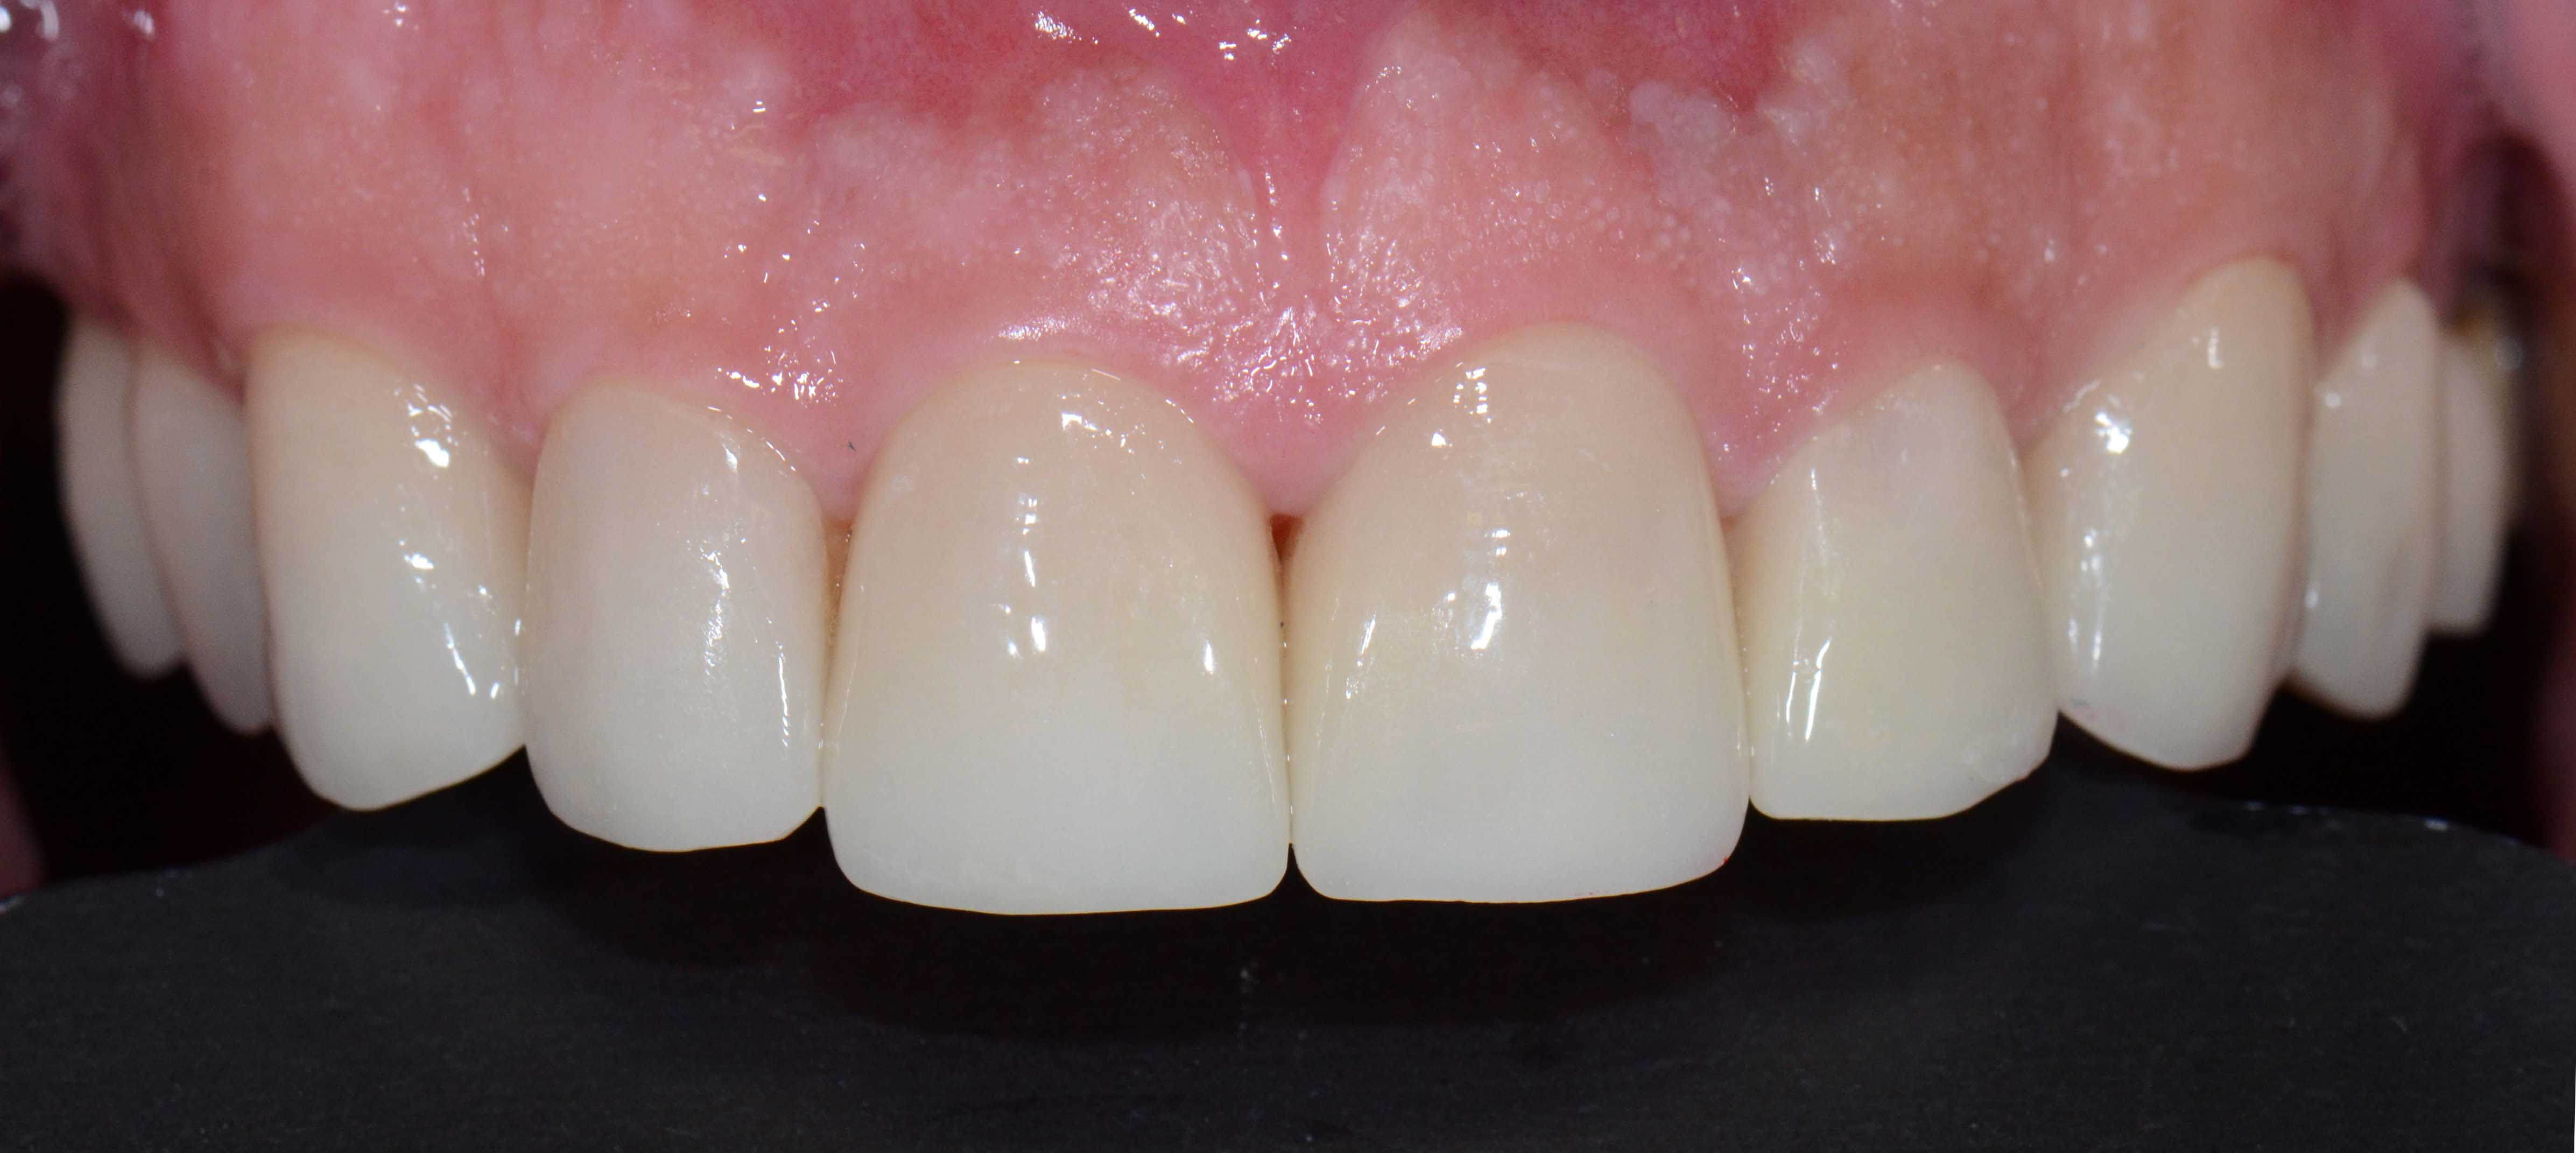

Tooth discoloration caused by tetracyclines

Aesthetic Rehabilitation with ceramic crowns and venners

Main problem:

Colour changes due to the use of tetracyclines as a child. Various treatments were done before to try to solve the problem but all of them were unsuccessful.

The Treatment:

Full crowns were opted to cover the teeth that were very damaged and venners were used to cover those who were less damaged and by doing this less natural tooth structure was damaged.